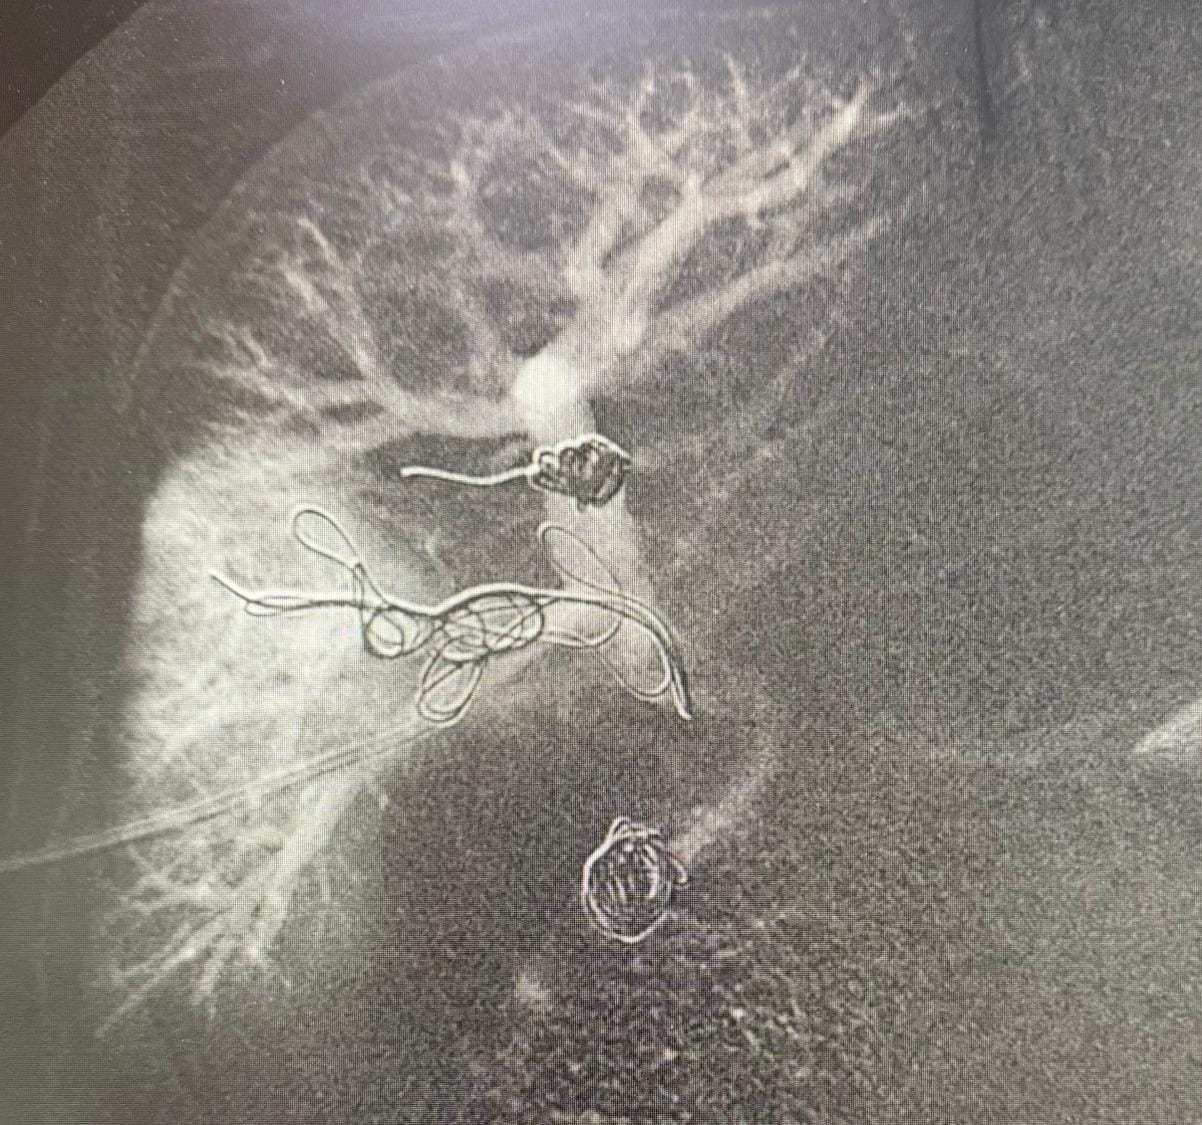

Imagem do fígado já com o controle final pós-embolização de veia porta

Como parte deste preparo, foi realizada a punção trans-hepática dos ramos portais direitos, seguida da embolização. Durante o procedimento, são introduzidos materiais específicos, como molas e partículas, nas veias do fígado, com o objetivo de interromper o fluxo sanguíneo na área afetada.